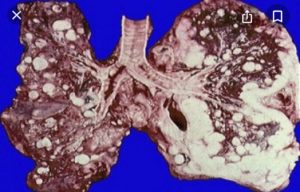

- Легкие. В этом органе метастазы имеют правильную круглую форму, плотную структуру и нежный розовый оттенок. Особенностью этих раковых опухолей является четкий легочный рисунок, сохраняющий свою природную форму. Попадая в организм через лимфатические железы в легкие, они за непродолжительное время захватывают всю поверхность органа. Размер раковой опухоли может составлять от одного до шести сантиметров.

Обратите внимание! Легкие, печеньи лимфатические узлы являются самыми распространенными органами, где распространяется метастазирование при различных онкологических заболеваниях.